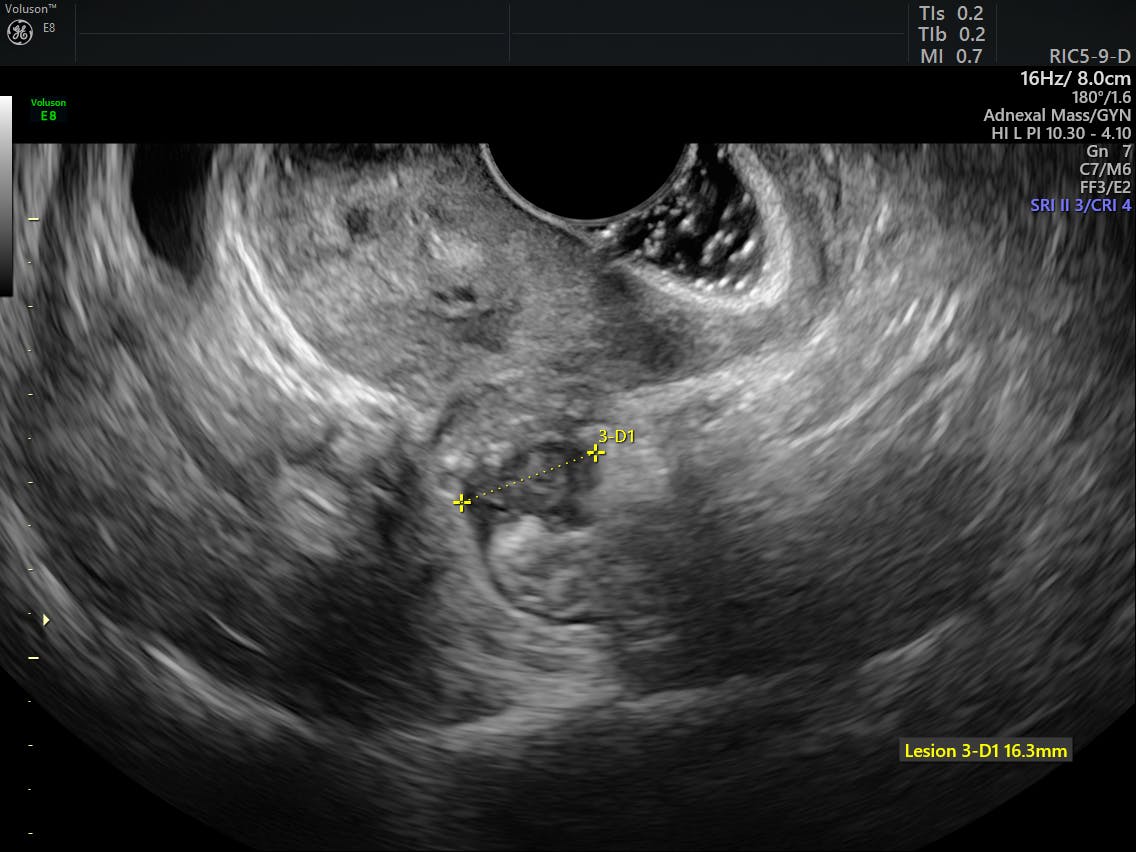

Transvaginal US of Endometriosis Looking Beyond the Endometrioma with Endometriosis Us Findings An endometriosis ultrasound is an imaging procedure that helps your. What is an endometriosis ultrasound? a dedicated transvaginal sonographic protocol for pelvic endometriosis has four components:. ultrasound is an effective tool to detect and characterize endometriosis. this statement defines the targeted screening population, describes techniques for augmenting pelvic us, establishes direct and indirect observations for endometriosis at. Endometriosis Us Findings.

Findings of Pelvic Endometriosis at Transvaginal US, MR Imaging, and Endometriosis Us Findings ultrasound is an effective tool to detect and characterize endometriosis. a dedicated transvaginal sonographic protocol for pelvic endometriosis has four components:. What is an endometriosis ultrasound? • endometriosis includes ovarian endometriomas, peritoneal implants and deep pelvic endometriosis. although laparoscopy is the gold standard test to establish a diagnosis. this statement defines the targeted screening population,. Endometriosis Us Findings.